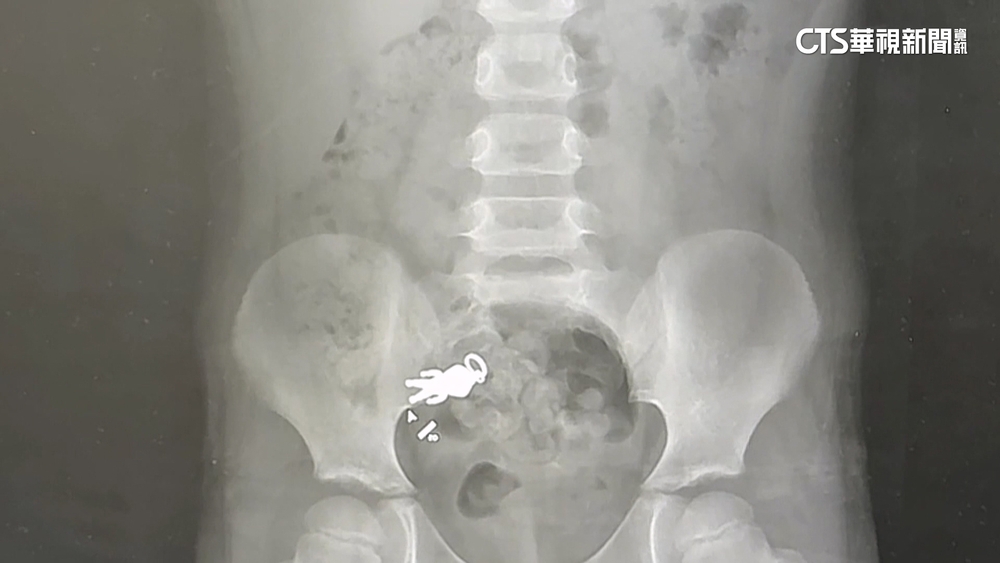

宜蘭童誤食「超人公仔」照X光現身! 網歪樓:附身合體

羅東博愛醫院小兒科主任謝錦桐說:「這是小朋友吞下去的這個超人形狀的吊墜。」這是小朋友吞下去的這個超人形狀的吊墜,X光影像中,一隻清晰可見的公仔,就藏在身體裡。

原來9月6日晚上,小朋友一邊看電視一邊吃餅乾,吃到一半說好像把玩具吃下肚了,等了兩天還是不見公仔身影,9月8日到醫院照X光果然發現公仔,叔叔將X光片PO上網,貼文吸引超過4萬人按讚,引發熱烈討論。

羅東博愛醫院小兒科主任謝錦桐說:「的確還在身體裡面,不過已經順利到達腸子的部分了,而且小朋友目前沒有任何症狀,那這個吊墜本身看起來,並沒有什麼尖銳的成分,看起來應該是可以順利排出的一個大小。」